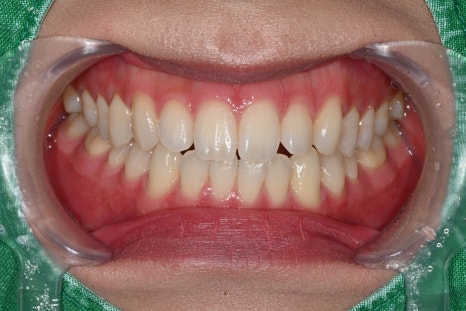

시술 전 사진

오브제로 시술 전 사진

오브제로 시술 전